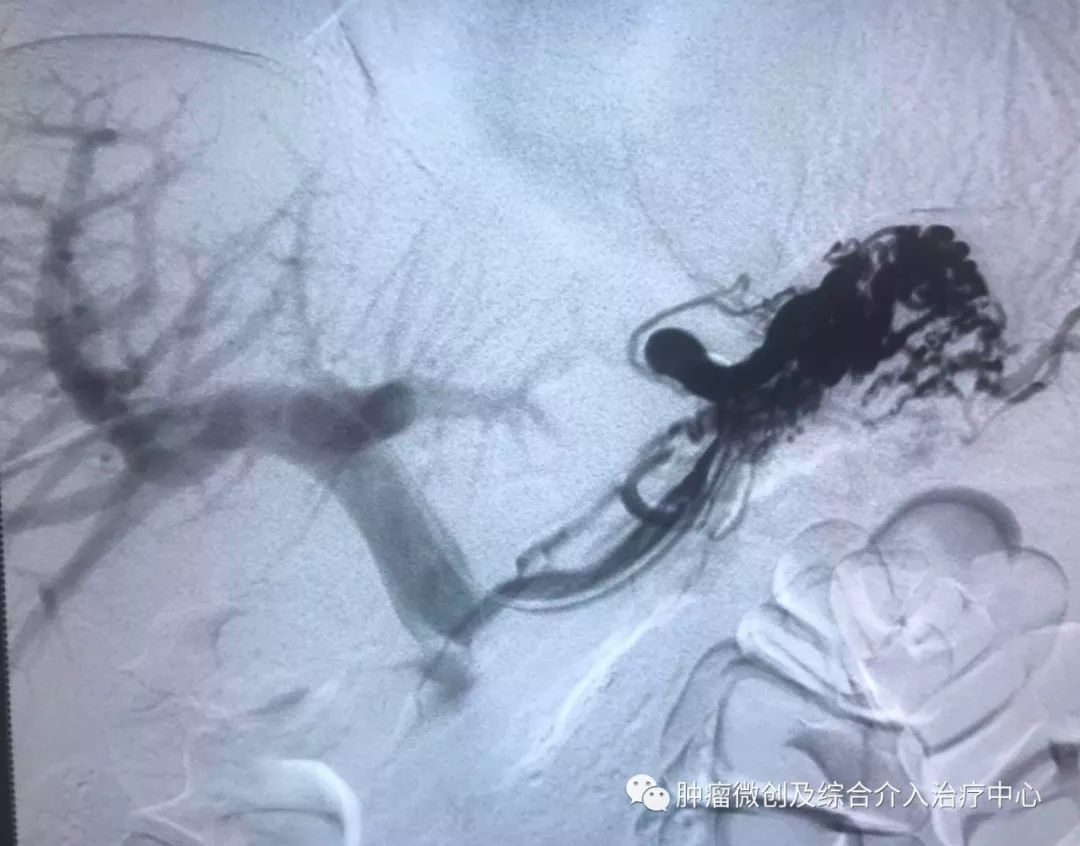

(鼻咽癌颈部转移瘤破溃出血,DSA造影提示左颈部病变血管迂曲、紊乱,内有出血)

(介入栓塞病变血管后,DSA示肿瘤病变血管栓塞好,血管走向清晰,出血停止)项目介绍:头颈部良、恶性肿瘤临床常见,其良性见于鼻咽纤维血管瘤,恶性者见于鼻咽、鼻窦癌,颈部转移性肿瘤等; 传统止血治疗疗效有限,给患者及家属带来极大的精神压力,介入手术栓塞病变血管可达到确切的止血效果,并致病变缺血萎缩。04急性肺栓塞介入手术治疗